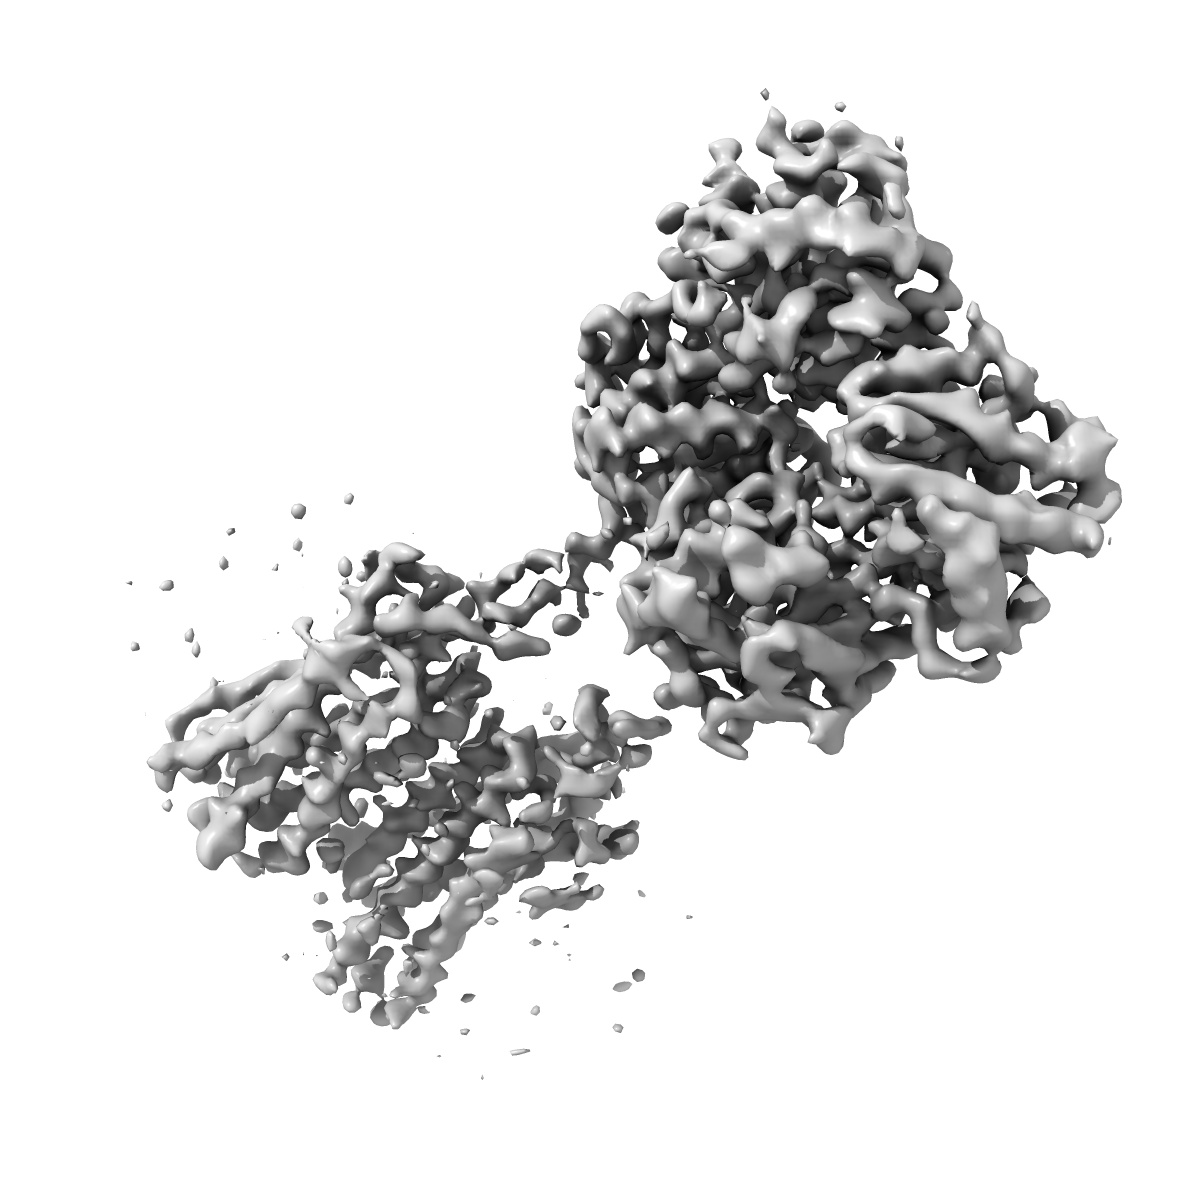

Cryo-EM structure of human GABA(B) receptor bound to the positive allosteric modulator rac-BHFF

Single-particle

4.5 Å

Fitted models: 7ca3